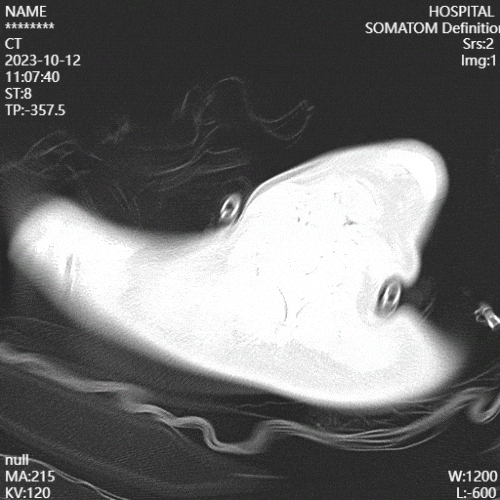

(5)康复措施及效果:复查影像学可见患者肺部炎性病变较前减少。

图片